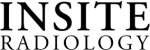

A state-of-the-art approach If prostate cancer is suspected, a biopsy may be required. With the assistance of a high-resolution prostate scan, a more refined, targeted biopsy is performed. At Insite, we use Dynacad software to fuse MRI and ultrasound images together to target potential prostate cancers in real time. The result is a highly-accurate targeting system that demonstrates the precise location of a possible cancer so that doctors can see what was, only a few years ago, often invisible. Our doctors were some of the earliest adopters of this technology and, as such, have acquired a level of experience with it that is exceedingly rare.

Some men may have elevated serum PSA levels, but a biopsy has not revealed any cancerous cells. A prostate MRI may reveal the presence of a tumor that could not be confirmed with a biopsy. Research into prostate cancer indicates that an MRI-directed biopsy can detect prostate cancer in between 34 to 41 percent of men who have a prior negative biopsy.

- Facilitates more accurate targeting of cancer lesions in a biopsy

- Can detect cancers that were undetected with a prior biopsy

- The result is a highly accurate targeting system that demonstrates the precise location of a possible cancer so that doctors can see what was, only a few years ago, often invisible.